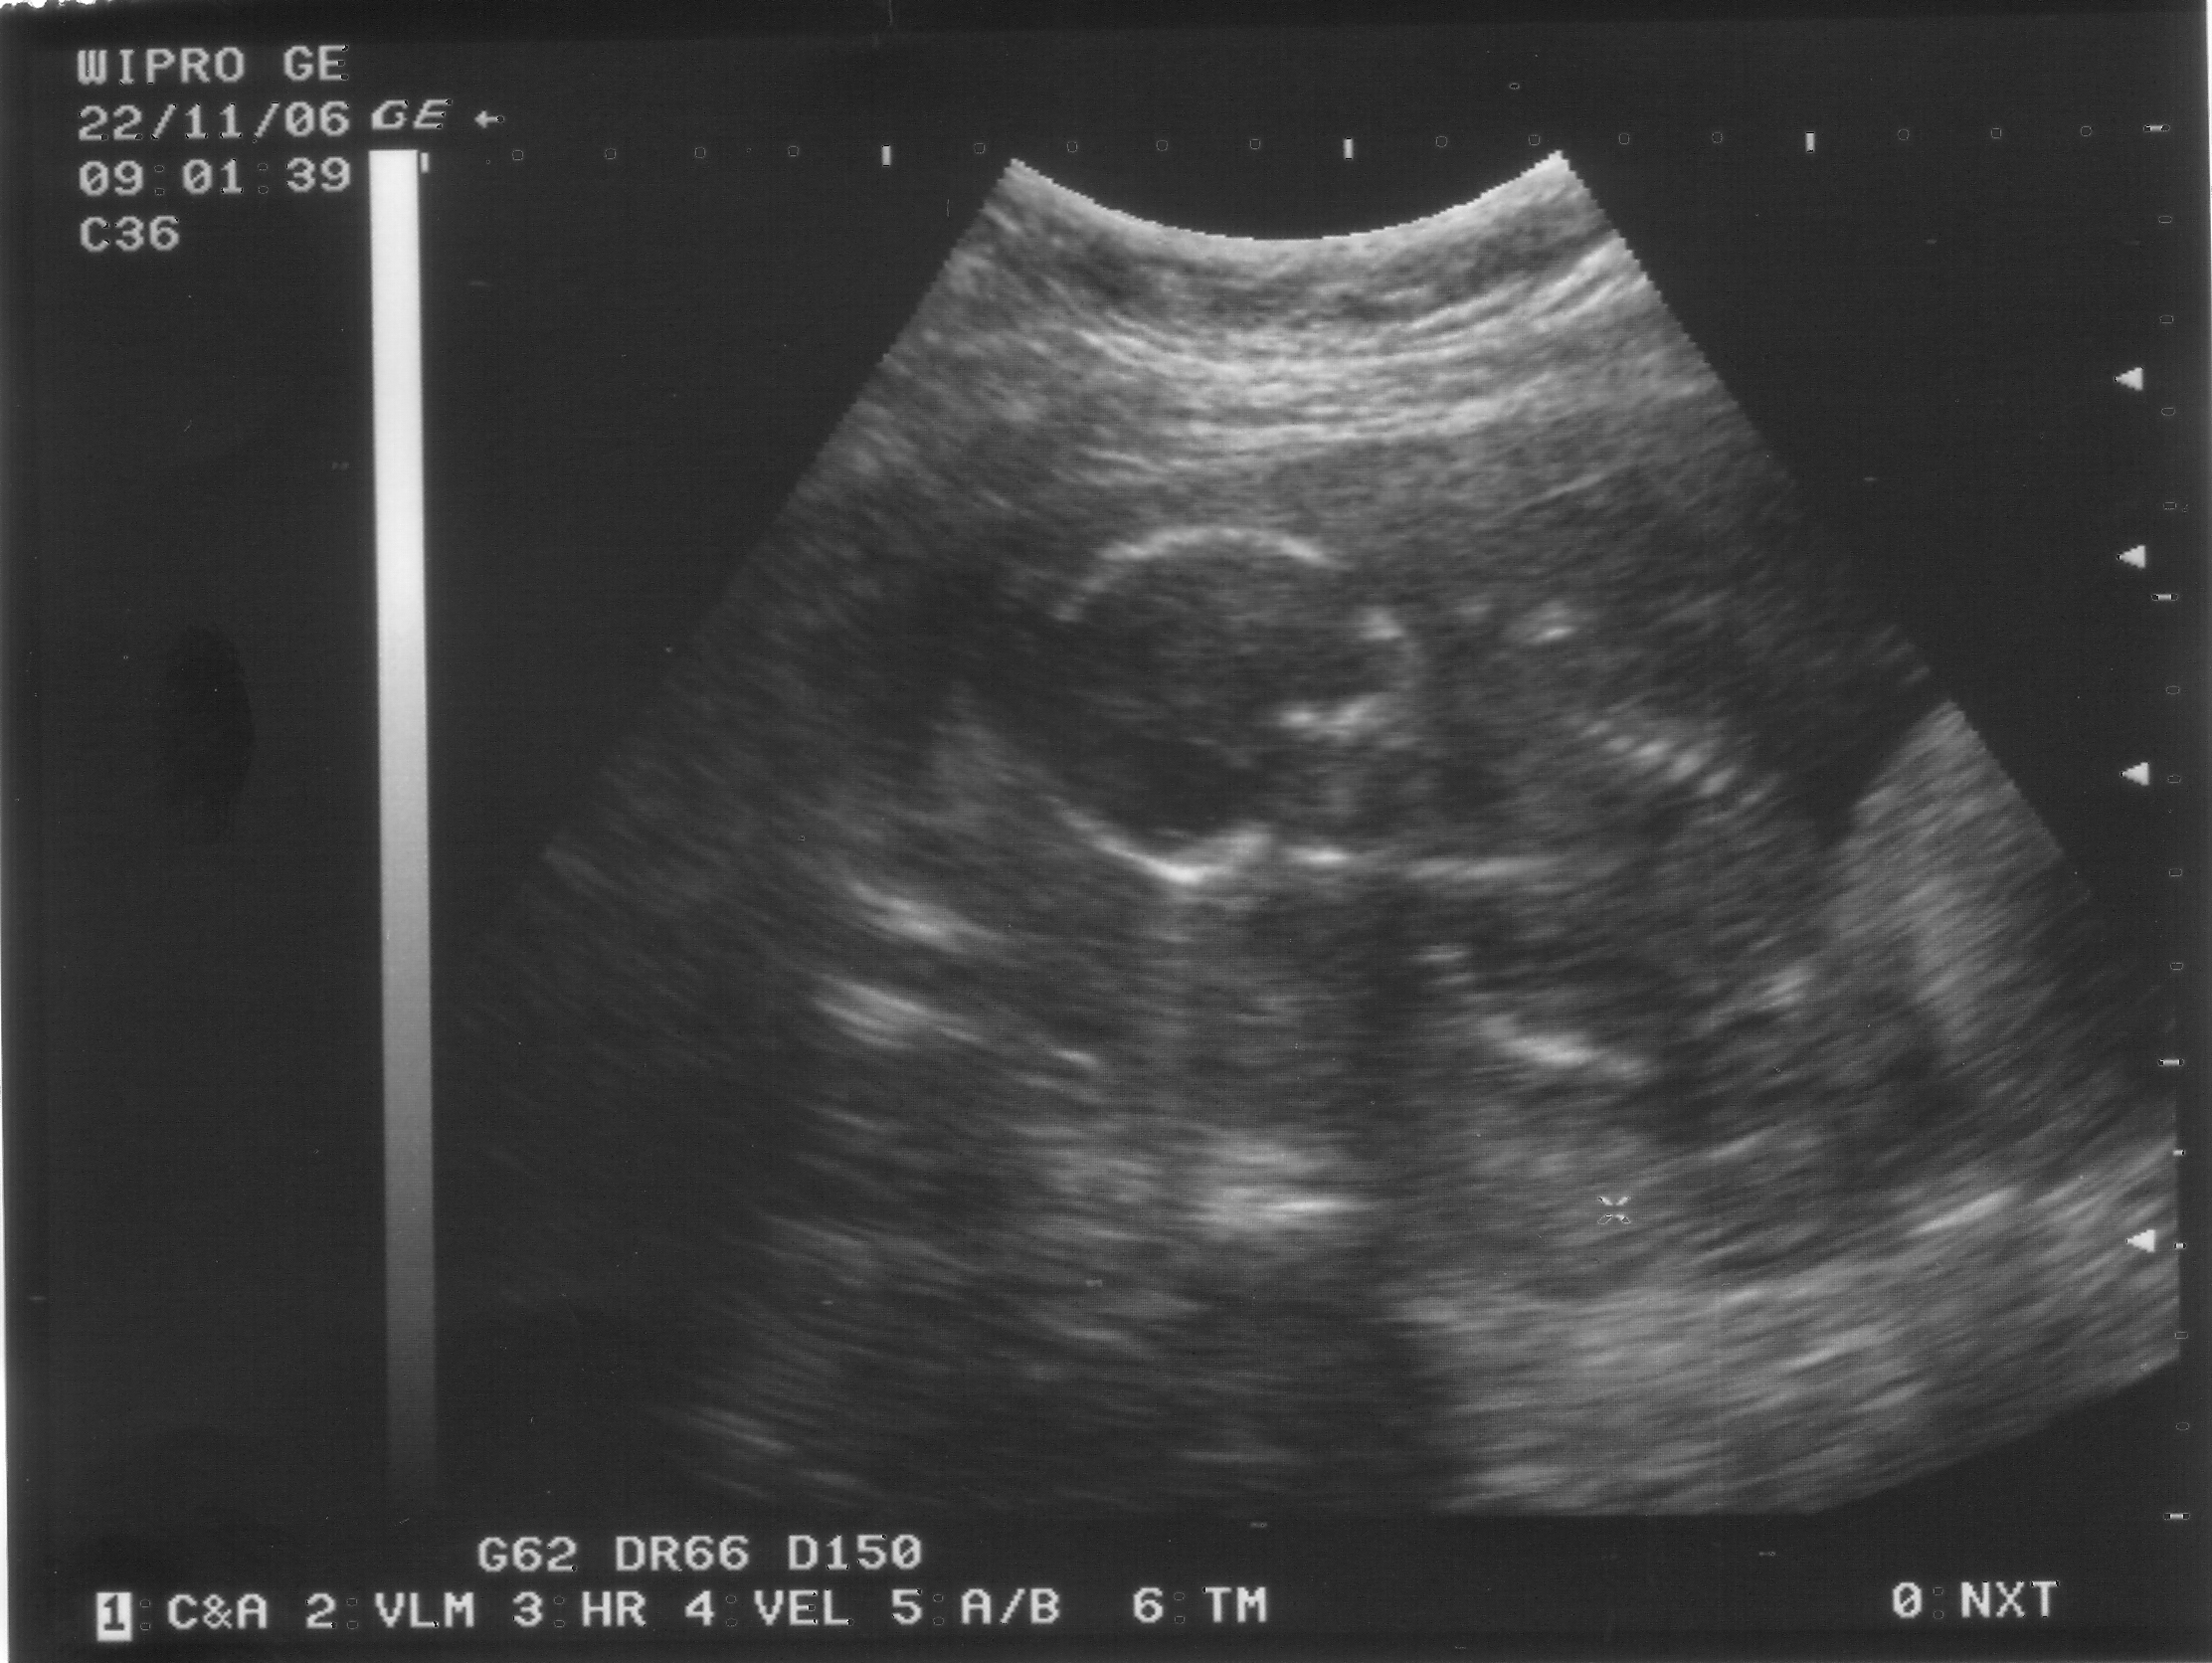

Дима - УЗИ, 16 недель, 22 ноября 2006